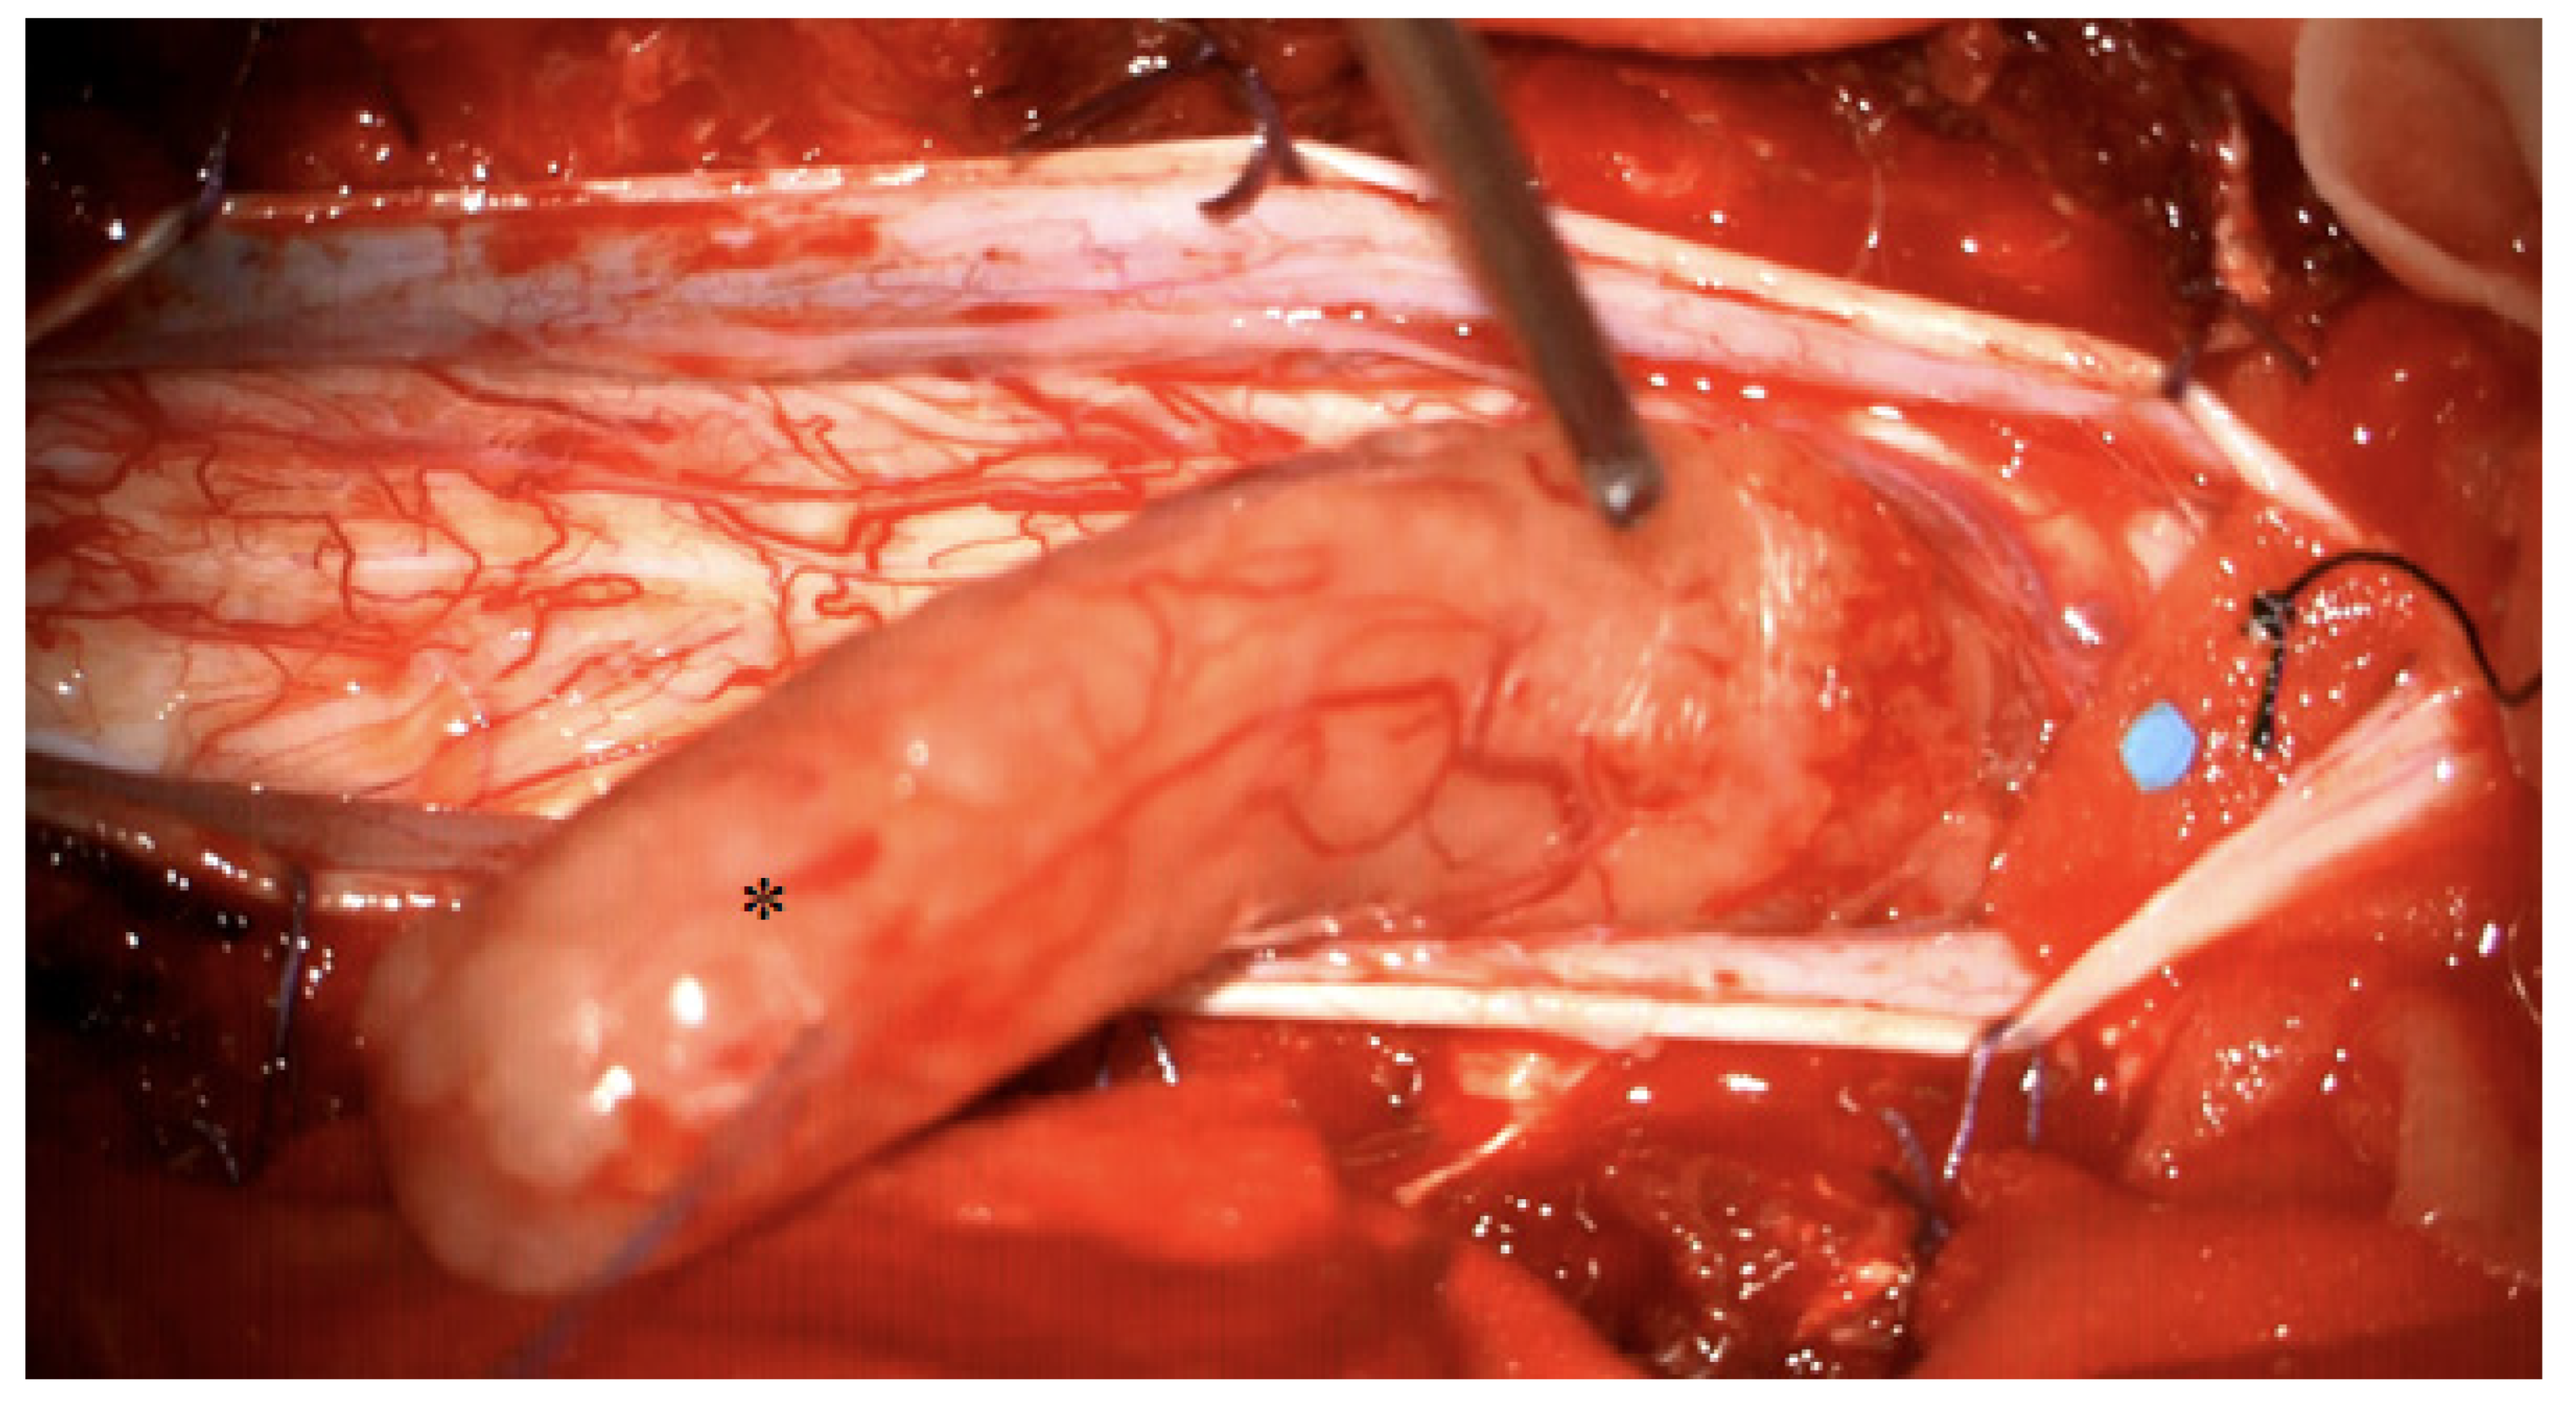

4. Illustrative Case